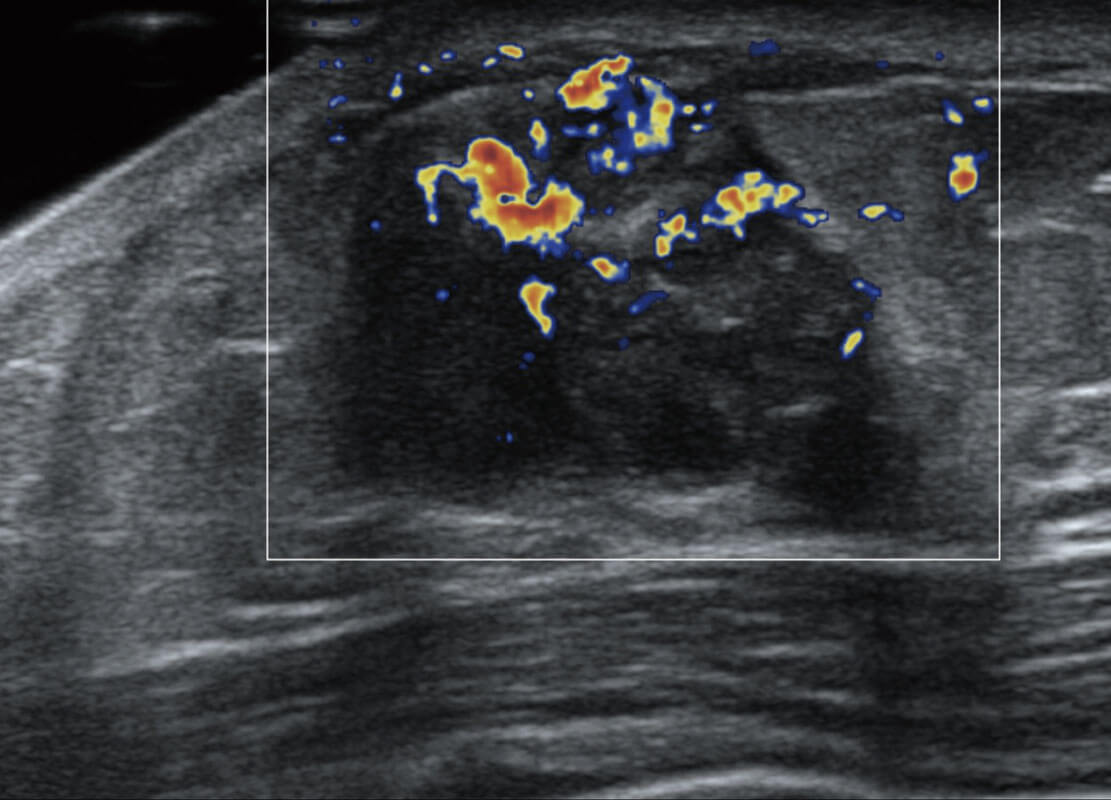

乳腺超声 / 新生儿

P60搭载宽频带线阵探头、宽景成像、弹性成像技术,为您提供乳腺应用方案。P60支持高频相控阵探头、线阵探头、腹部高频探头、腹部微凸探头等,丰富的探头群搭载敏感的彩色血流成像,适用于新生儿多种脏器检测要求,满足新生儿筛查需求。

• 乳腺导管癌

• 乳腺癌显微血流

• 新生儿肝血管癌